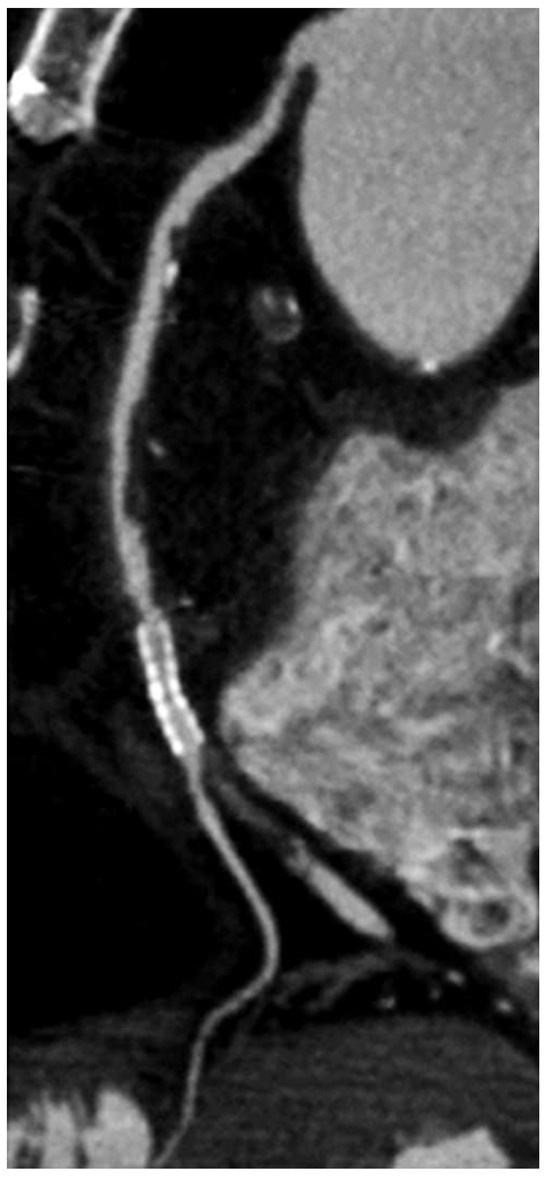

Propofol-Dip for Tricky Stent Delivery

by Lukas Burri, Mario Togni and Stéphane Cook

Cardiovasc. Med. 2013, 16(5), 153; https://doi.org/10.4414/cvm.2013.00137 - 22 May 2013

A 70-year-old male patient was referred for closure of patent foramen ovale after recurrent transient cerebral ischaemia [...] Full article